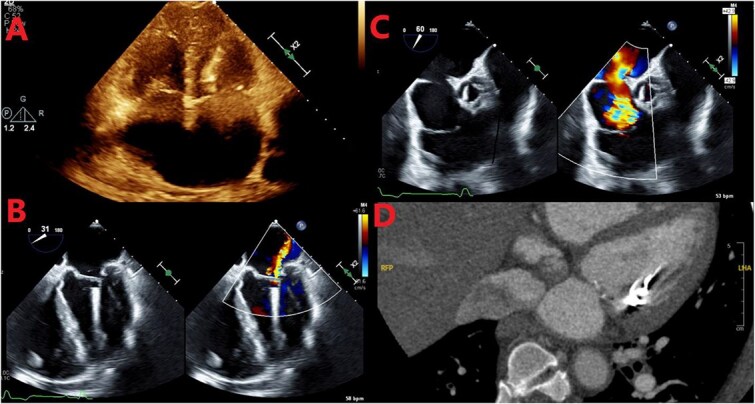

导读:无铅心内起搏器(LICPs)减少了与铅相关的并发症,但可能在有未被识别的结构缺陷的患者中定位不当。我们报告了一名69岁男性患者,其高级别房室传导阻滞,其LICP原计划放置于右心室,在16个月后出现多灶栓塞性中风,经未确诊的第二口ASD在左心室被发现。病例介绍:急性右侧症状的卒中检查显示左室LICP和一个大的,以前未诊断的ASD,双向分流和严重的肺动脉高压。栓塞性梗死可归因于矛盾栓塞或器械相关的血栓栓塞。由于手术风险高,设备被留在原位;肝素开始时计划与华法林衔接。患者后来拒绝了经皮ASD闭合术。结论:本病例强调了LICP通过未被识别的ASD而错位的风险,并强调了在植入前进行结构评估的必要性,即使没有临床怀疑。

Introduction: Leadless intracardiac pacemakers (LICPs) reduce lead-related complications but may be malpositioned in patients with unrecognized structural defects. We report a 69-year-old man with high-grade AV block whose LICP, intended for right ventricular placement, was found in the left ventricle via an undiagnosed ostium secundum ASD after presenting with multifocal embolic strokes 16 months later. Case Presentation: Stroke workup for acute right-sided symptoms revealed the LICP in the LV and a large, previously undiagnosed ASD with bidirectional shunting and severe pulmonary hypertension. Embolic infarcts were attributed to either paradoxical embolism or device-related thromboembolism. Due to high surgical risk, the device was left in place; heparin was started with plans to bridge to warfarin. The patient later declined percutaneous ASD closure. Conclusion: This case highlights the risk of LICP misplacement via an unrecognized ASD and underscores the need for structural evaluation before implantation, even without clinical suspicion.